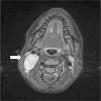

Niña de 13 años con tumoración cervical derecha detectada por la paciente desde hace unos 3 meses. A la palpación, bultoma de 3×4cm, de consistencia dura, adherido a planos profundos, sin inflamación ni dolor. No hay antecedente de proceso infeccioso, fiebre o síntomas constitucionales. La analítica sanguínea y la radiografía de tórax fueron normales. En la ecografía cervical se evidenció una masa en el espacio carotídeo derecho, de 4×2×4cm, de forma ovoidea, bien delimitada, isoecoica al músculo y con abundante vascularización en su interior. Estos hallazgos hicieron sospechar una tumoración de origen neural. Se completó el estudio con una resonancia magnética cervical. Las imágenes obtenidas (figs. 1 y 2) confirmaron como primera opción la sospecha de un schwannoma del vago, dada la morfología fusiforme de la lesión, con eje mayor longitudinal siguiendo el trayecto del nervio (fig. 3). Se realizó resección completa de la tumoración dependiente de la rama nerviosa cervical. El estudio histológico confirmó el diagnóstico de schwannoma del nervio vago. La paciente presentó síndrome de Horner derecho posquirúrgico sin otras complicaciones. Tras 6 meses no existe evidencia de recidiva tumoral.